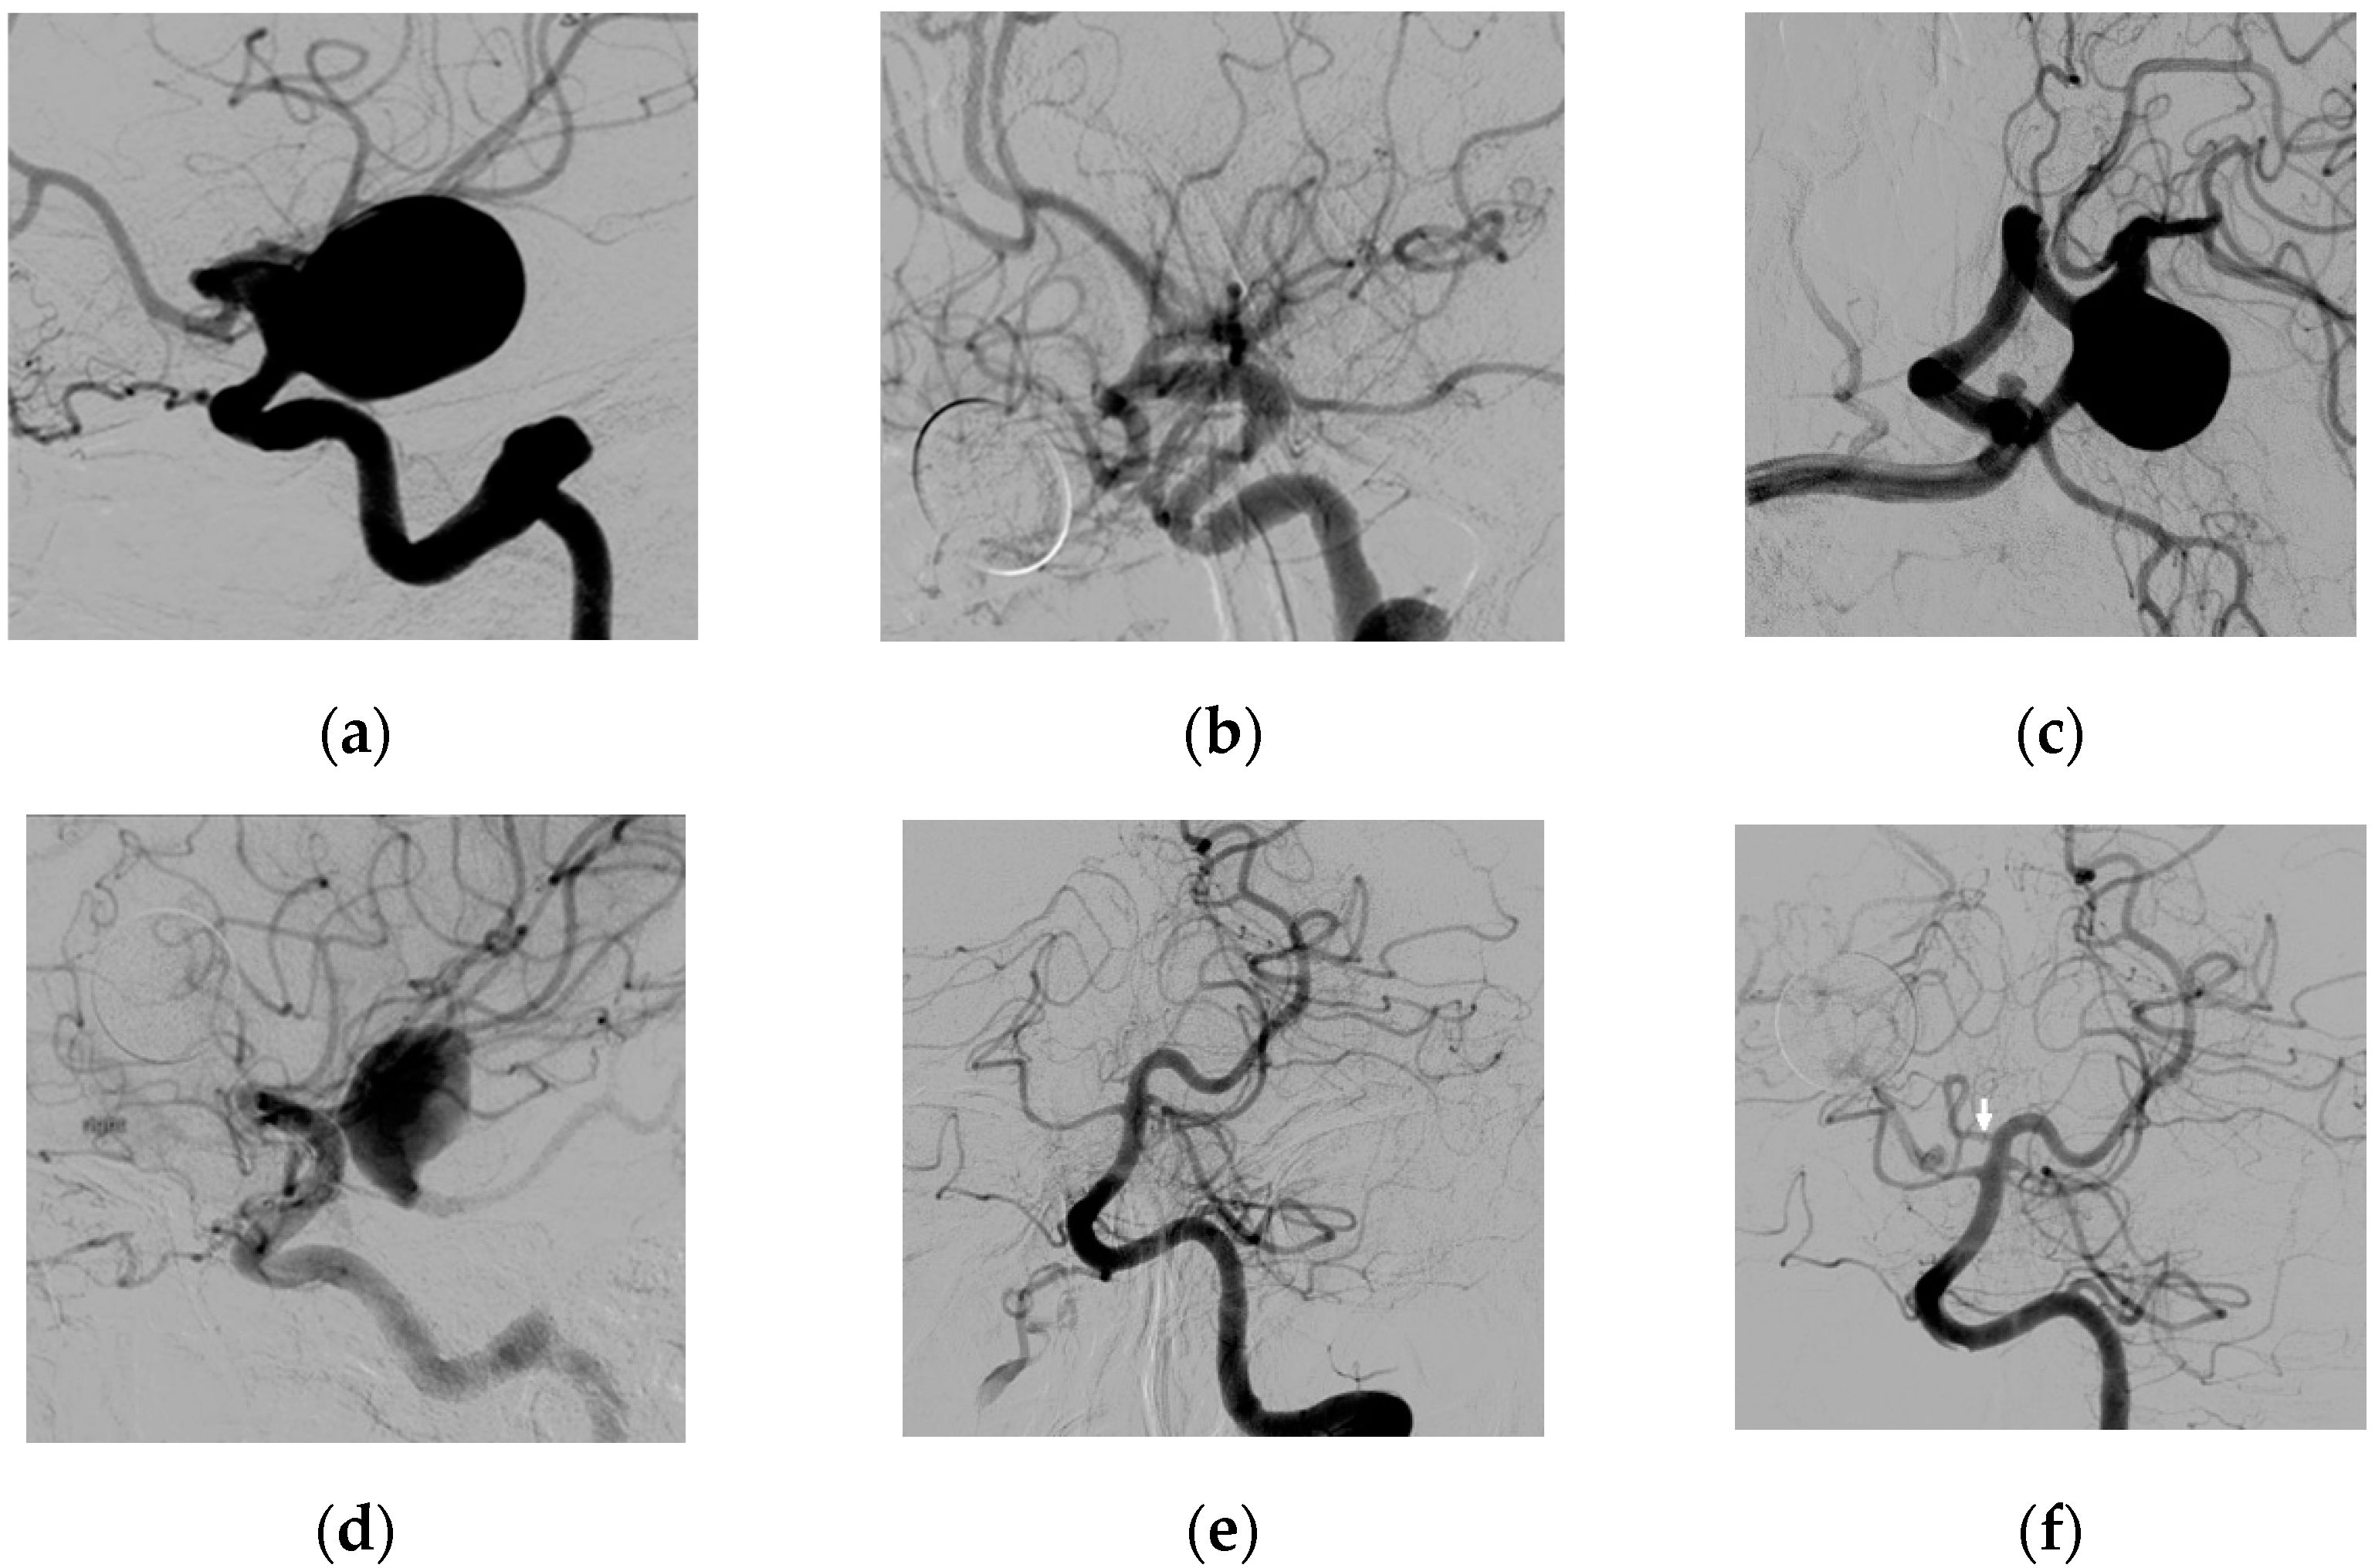

3.2. Fetal Type PcomA Patients